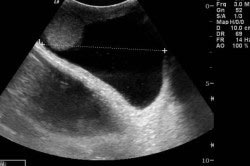

Для постановки точного диагноза необходимо проведение внешнего осмотра мошонки, диафаноскопии и пальпации. В некоторых случаях для постановки диагноза требуется проведения УЗИ, чтобы исключить грыжу, имеющую схожую симптоматику. При подтверждении гидроцеле назначается операция.